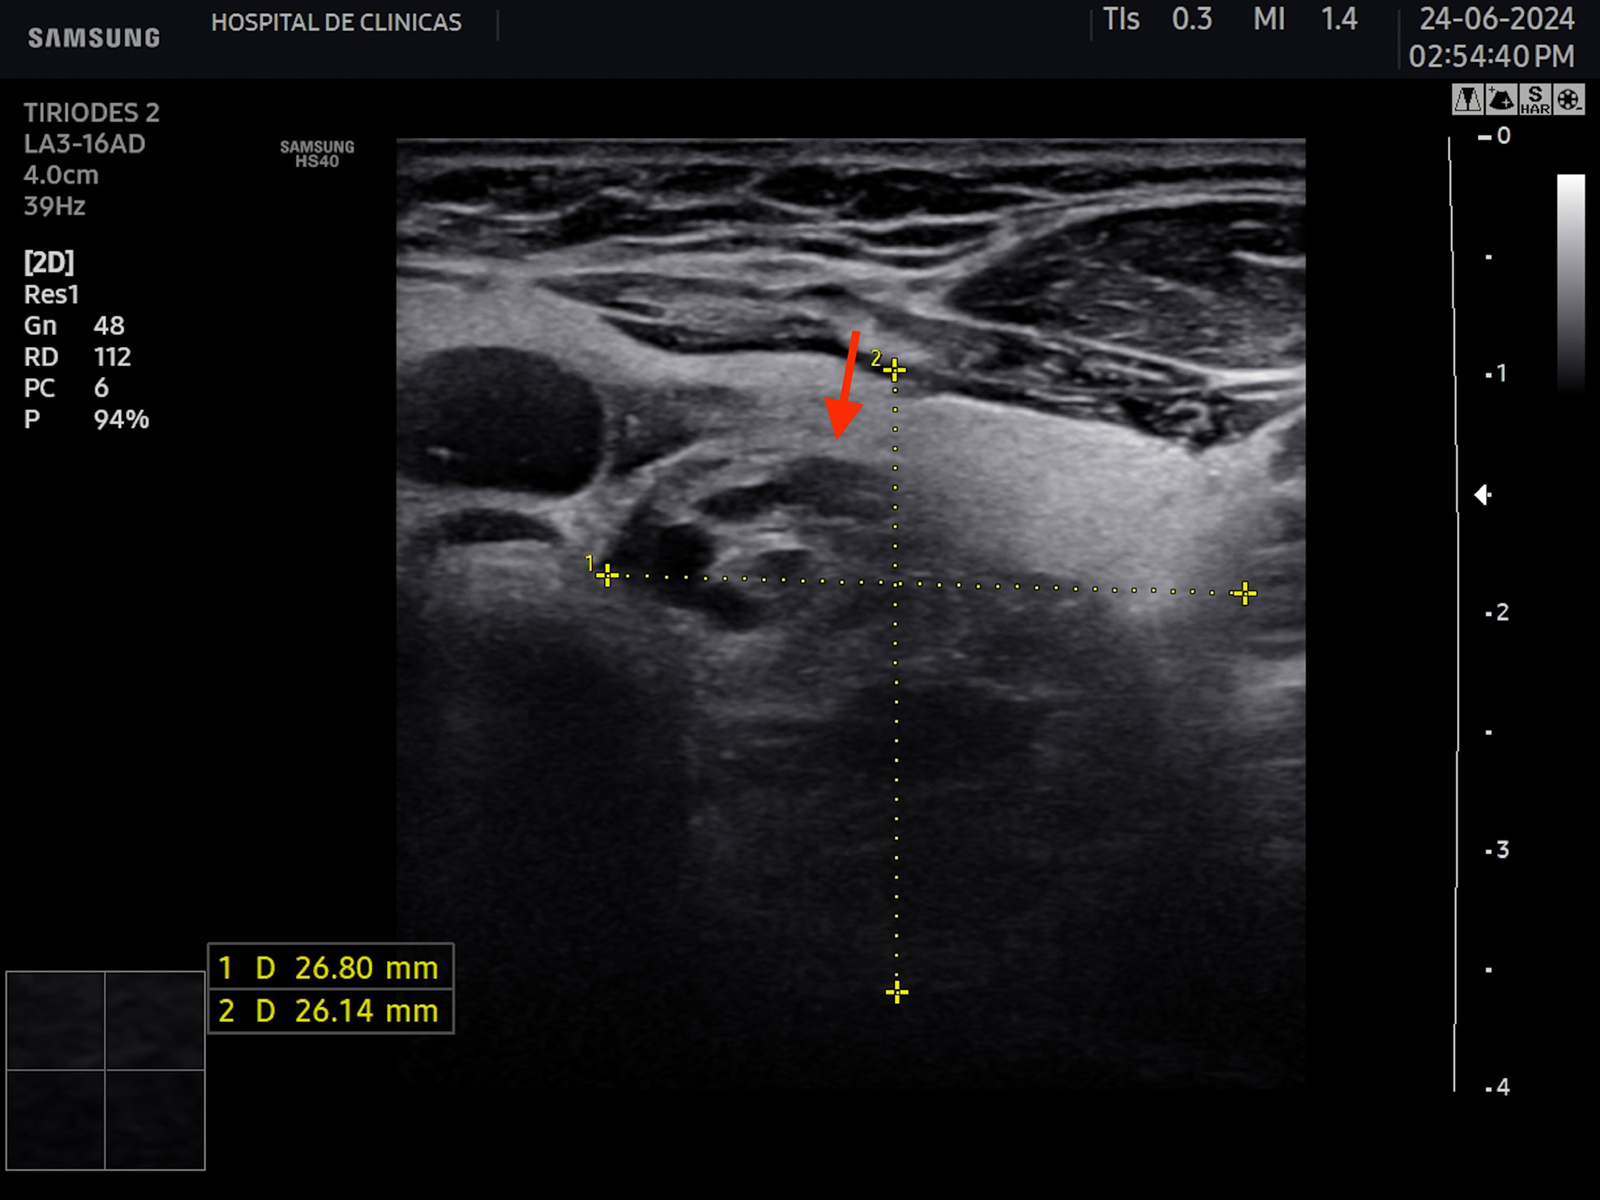

La fase aguda es transitoria, generalmente comienza con infiltración linfocítica en el istmo y en los sectores anteriores de los lóbulos tiroideos representados con manchas hipoecoicas homogéneas y uniformes, además de áreas con márgenes mal definidos. La propagación de la infiltración confiere este aspecto en ambos lóbulos. En la fase subaguda se propaga esta infiltración al resto de la glándula acompañada de hipervascularización irregular7.

La hipoecogenicidad del parénquima glandular se correlaciona con el grado de infiltración linfocitaria, atrofia de los folículos y disminución del contenido coloide. Esto genera menos reflexión de las ondas sonoras y, por lo tanto, menor ecogenicidad6. Se puede encontrar además aspecto micro o macronodular. Se denominan seudonódulos a las áreas de intensa infiltración linfocitaria local, las cuales deben ser diferenciadas de los nódulos verdaderos que requieren otro seguimiento6. En la figura 6 se aprecian estas características comentadas.

Figura 6: Corte transversal y longitudinal de tiroides de paciente con tiroiditis de Hashimoto. Se señala la disminución de la ecogenicidad, estructura

heterogénea, seudonodular.

Con respecto a la vascularización con doppler color, se encuentra normal o disminuida en un 63%, moderadamente aumentada en un 18% y muy aumentada en un 7% de los casos6. Se observa mayor vascularización en la enfermedad de inicio reciente, especialmente en los casos sin tratamiento, que presentan mayor volumen tiroideo con niveles de anticuerpos y hormona estimulante de la tiroides (TSH) más elevados6.